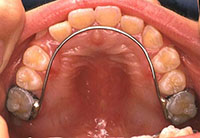

リンガルアーチ

歯の裏側から使用するアーチ状の装置です。奥歯が前にくるのを防いだり、内側から歯を押すことで口腔内を広げながら歯並びを整えていきます。

前からは見えません。

リンガルアーチを装着

| 初診時年齢・性別 | 7歳8ヶ月 男性 |

|---|---|

| 主訴 | 前歯のかみ合わせが逆 |

| 診断名・主な症状 | 前歯部の反対咬合 下の顎が広がってきている |

| 治療内容 | 上顎にはリンガルアーチ、下顎にはバイトプレート装置を使って治療 |

| 治療期間 | 7ヶ月 |

| 注意点・リスクなど | 矯正治療による伴う痛み、慣れるまで舌感が気になる、歯磨きがしづらくなる |

| 治療費用 | 約10万円 |

リンガルアーチを使っての治療。

| 初診時年齢・性別 | 6歳9ヶ月 男性 |

| 主訴 | かみ合わせが逆 |

| 診断名・主な症状 | 前歯部の反対咬合 |

| 治療内容 | 上顎にリンガルアーチを使って治療 |

| 治療期間 | 6ヶ月 |

| 注意点・リスクなど | 矯正治療による伴う痛み、歯磨きがしづらくむし歯リスクがでる |

| 治療費用 | 約6万円 |